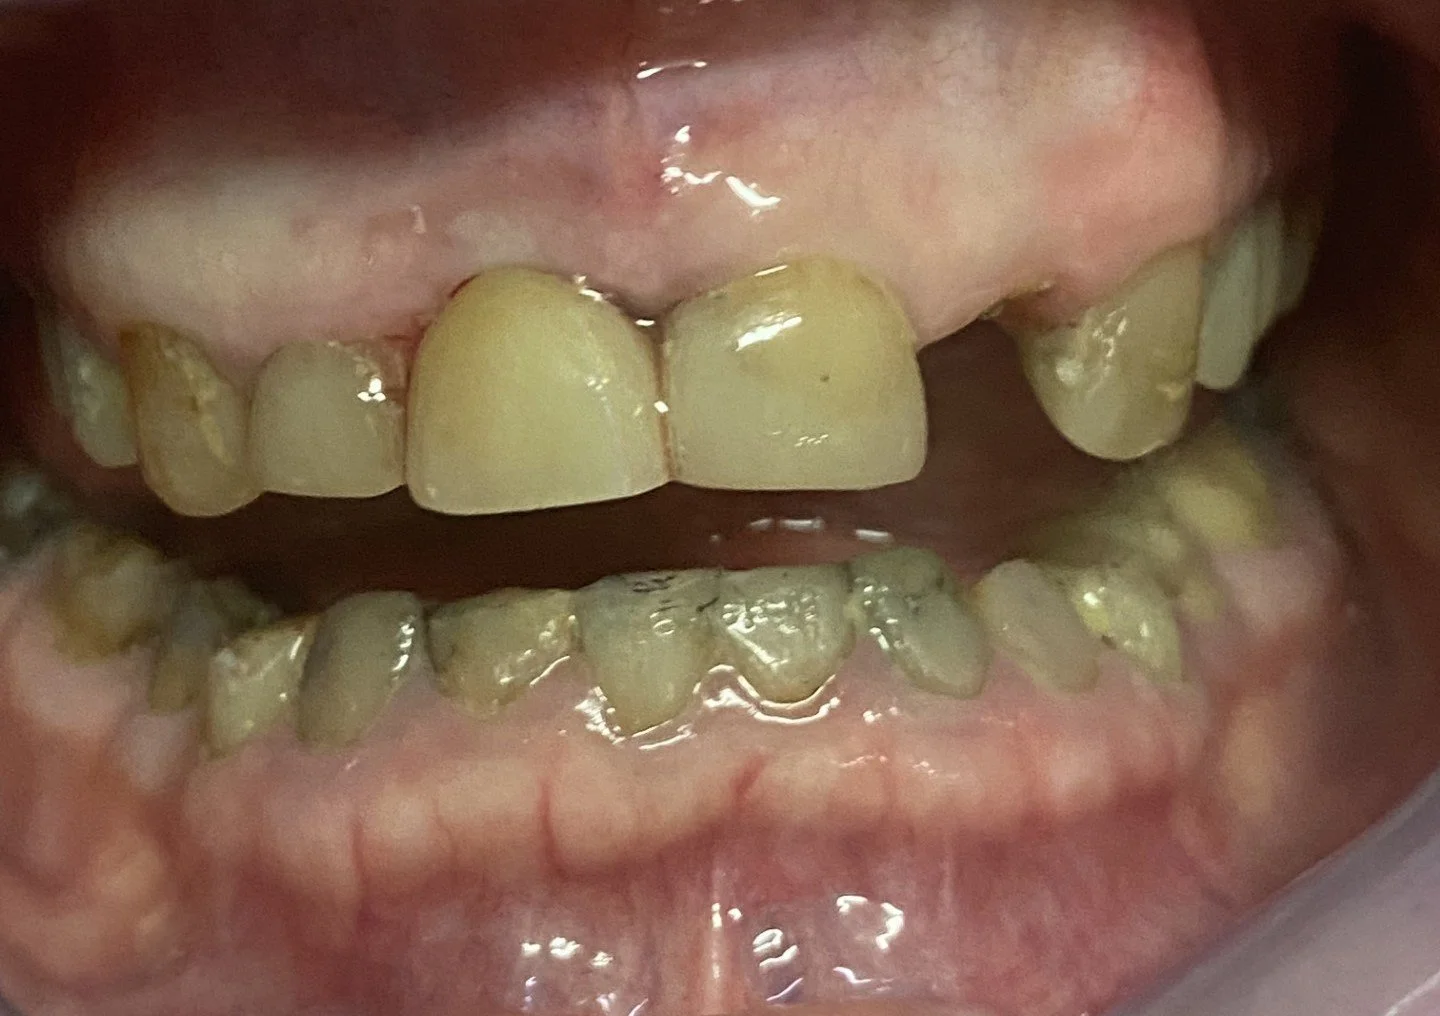

This 65 year old patient had numerous dental problems including decay, periodontal gum disease involving moderate to concerning future bone loss, missing teeth, heavily filled teeth and an extremely difficult very deep overbite.

Part of the deep overbite and a heavily discoloured top left number 2 lateral incisor previously extracted, root sectioned and amalgam filled prior to reattaching as a bonded bridge tooth to the adjacent top left number 3 canine tooth.

The remaining lower 6 front teeth that were deemed to have insufficient bone for longevity and unsuitable for a bite reconstruction, these teeth were extracted.